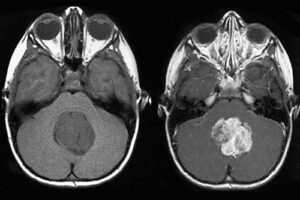

Медуллобластома является высокозлокачественной опухолью, развивающейся при патологических изменениях медуллобластов и локализованной в черве или полушариях мозжечка. От других онкозаболеваний мозговых тканей отличается быстрым метастазированием, которое осуществляется по ликворным путям.

- визуализирующие исследования — с помощью КТ, МРТ и ПЭТ-КТ удается выявить новообразование, подробно описать его структуру и другие особенности, оценить состояние мозговых структур, обнаружить самые мелкие отдаленные метастатические очаги;